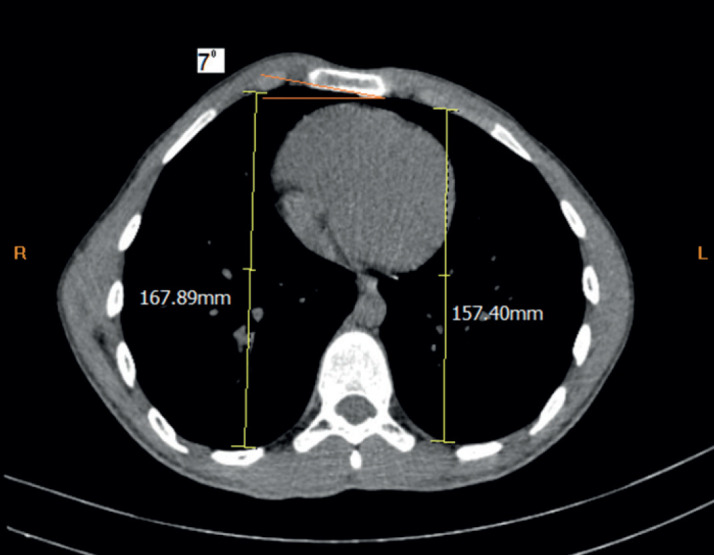

Results: Among 115 patients (mean age: 13.6 ± 2.03 years), the majority presented with symmetrical deformities (70.4%). The average operative duration was 33.3 ± 8.3 minutes, and hospital stays ranged from 4 to 7 days (mean: 5.2 ± 0.90 days). No major postoperative complications were reported. Follow-up ranged from 11 to 48 months. Chest CT Scan reevaluation postoperatively in 69 patients showed significant improvement in thoracic indices: mean pre- and postoperative Haller index (HI) were 2.02 ± 0.20 and 2.46 ± 0.34, respectively. Sternal rotation angle averaged 2.81 ± 3.59, with 68/69 cases showing no or mild torsion. Postoperative asymmetry index (AI) averaged -0.014 ± 0.033.

Conclusion: The modified Abramson technique provides a minimally invasive and effective treatment for pectus carinatum, achieving significant improvements in thoracic morphology as evidenced by Haller index, asymmetry index, and sternal rotation angles assessed on chest CT.